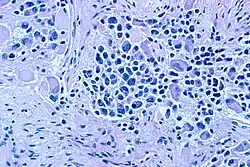

Microscopic view of a typical neuroblastoma with rosette formation

Microscopic view of stroma-rich ganglioneuroblastoma

On microscopy, the tumor cells are typically described as small, round and blue, and rosette patterns (Homer Wright pseudorosettes) may be seen. Homer Wright pseudorosettes are tumor cells around the neuropil, not to be confused with a true rosettes, which are tumor cells around an empty lumen.[29] They are also distinct from the pseudorosettes of an ependymoma which consist of tumor cells with glial fibrillary acidic protein (GFAP)–positive processes tapering off toward a blood vessel (thus a combination of the two).[30] A variety of immunohistochemical stains are used by pathologists to distinguish neuroblastomas from histological mimics, such as rhabdomyosarcoma, Ewing's sarcoma, lymphoma and Wilms' tumor.[31]

Neuroblastoma is one of the peripheral neuroblastic tumors (pNTs) that have similar origins and show a wide pattern of differentiation ranging from benign ganglioneuroma to stroma-rich ganglioneuroblastoma with neuroblastic cells intermixed or in nodules, to highly malignant neuroblastoma. This distinction in the pre-treatment tumor pathology is an important prognostic factor, along with age and mitosis-karyorrhexis index (MKI). This pathology classification system (the Shimada system) describes "favorable" and "unfavorable" tumors by the International Neuroblastoma Pathology Committee (INPC) which was established in 1999 and revised in 2003.[32]